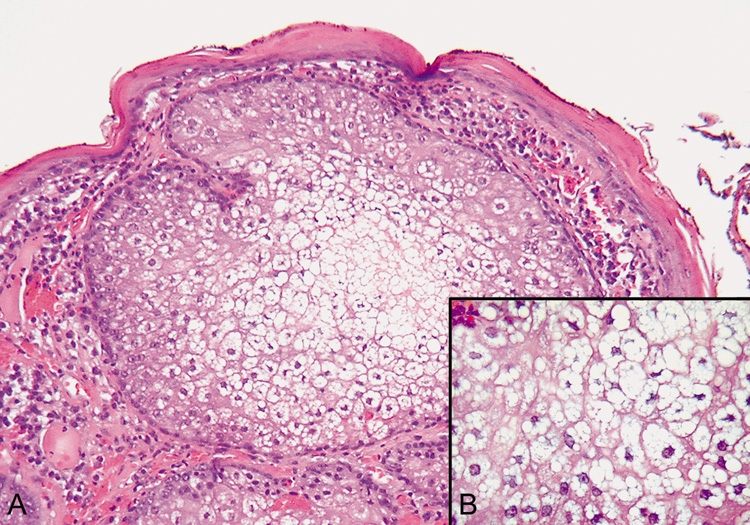

Lesions of molluscum contagiosum often affect the periorbital and lid skin as 1- to 3-mm domeshaped papules with a small central dell. This large pox virus multiplies in the cytoplasm, and, histologically, homogeneous purple intracytoplasmic inclusion bodies (molluscum bodies) are seen in an acanthotic epidermis (see Fig. 7).

Fig. 7. Molluscum Contagiosum—A. Umbilicated lesions typical of molluscum contagiosum on the upper lid of a child. Infection near the edge of the lid may cause a toxic follicular conjunctivitis. B. Low-power photomicrograph demonstrating crater shape of excised lesion (hematoxylin and eosin stain). C. High-power photomicrograph illustrating the large clumps of eosinophilic viral inclusions in the epithelial cells (“molluscum bodies“) (hematoxylin and eosin stain). (Photos courtesy of William Morris, M.D.)